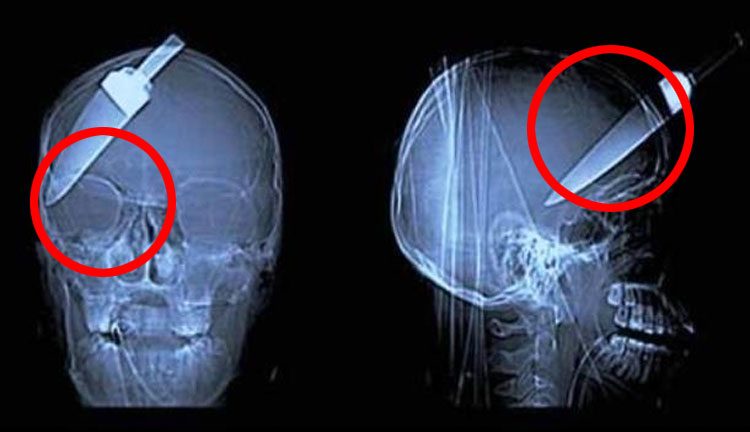

10. A pesar de lo que puedas pensar, un frasco de café instantáneo no ayudará a tu digestión

15. Una flecha atravesó la cabeza de un niño en China. Sobrevivió, pero estos rayos X serán un recordatorio de lo cerca que estuvo